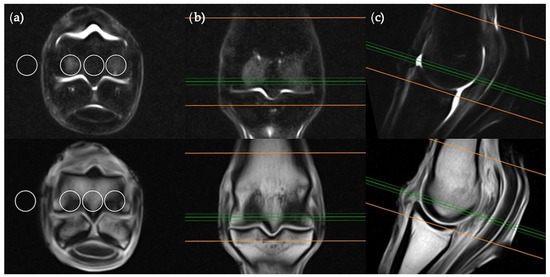

Images were viewed by a veterinary radiologist experienced with the interpretation of low-field equine fetlock MRI examinations (AY). MRI studies were viewed in “digital imaging and communications in medicine” (DICOM) format on an interactive DICOM viewer workstation (Osirix MD). Standardised regions of interest (ROIs) of 2 cm2 were imported into each study. The ROIs were positioned in predetermined locations for each plane of the STIR sequences (Figure 1, Figure 2, Figure 3 and Figure 4) then copied across to the corresponding T1W slice. For every intraosseous ROI measured, a background ROI was also placed external to the anatomy in the same image at a consistent, predetermined location. One to three signal to noise ratios (SNRs) were calculated for each image examined in order to evaluate signal changes between images rather than absolute signal value. SNR is the ratio between the amplitude of the MR signal of a tissue and the standard deviation of the amplitude of the background noise. Use of SNR also allowed for image window and level settings to be adjusted subjectively for each study in order to maximize visualization of intraosseous STIR hyperintensity. Each limb was graded poor, satisfactory, good or excellent for quality of fat suppression in the STIR sequences. The experimental protocol was divided into two parts; blinded and unblinded.

The sagittal plane measurements required three different images for ROI placement; parasagittal slices through the centre of the lateral and medial condyles of the third metacarpal/metatarsal bone (Figure 3) as well as a third image on sagittal midline (Figure 4). In the absence of an image perfectly centred of any of these anatomical locations then the adjacent image containing the greatest amount of STIR hyperintensity was chosen. This was commonly required for the sagittal image ROI. Condylar ROIs were placed at the edge of the subchondral bone plate within the centre of the palmar/plantar half of the lateral and medial condyles. The axial physeal ROI was placed within the axial portion of the bone at the level of the physeal vasculature. The background ROI was placed at the dorsal surface of the limb, proximal to the sagittal ridge of the third metacarpal/metatarsal bone.

Figure 3. STIR FSE (top row) and T1W GRE (bottom row) MRI images in (a) transverse; (b) frontal and (c) sagittal planes; demonstrating the location of condylar ROI placement in a parasagittal plane. The green lines on the transverse and frontal images show the standardized orientation and location of the medial or lateral condylar parasagittal slices for ROI placement. The orange lines show the extent and orientation of all the sagittal slices acquired in the MRI study.